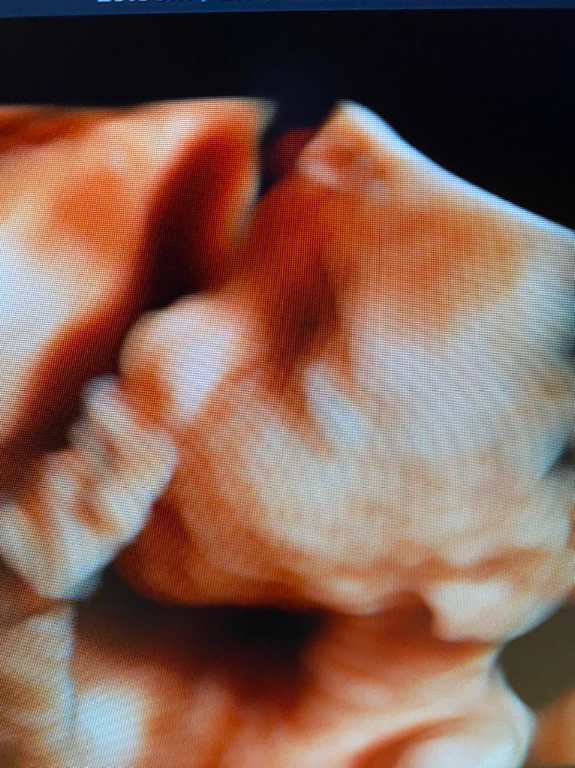

Atención de parto

Envíado por Dra. Erika Lissette Palacios